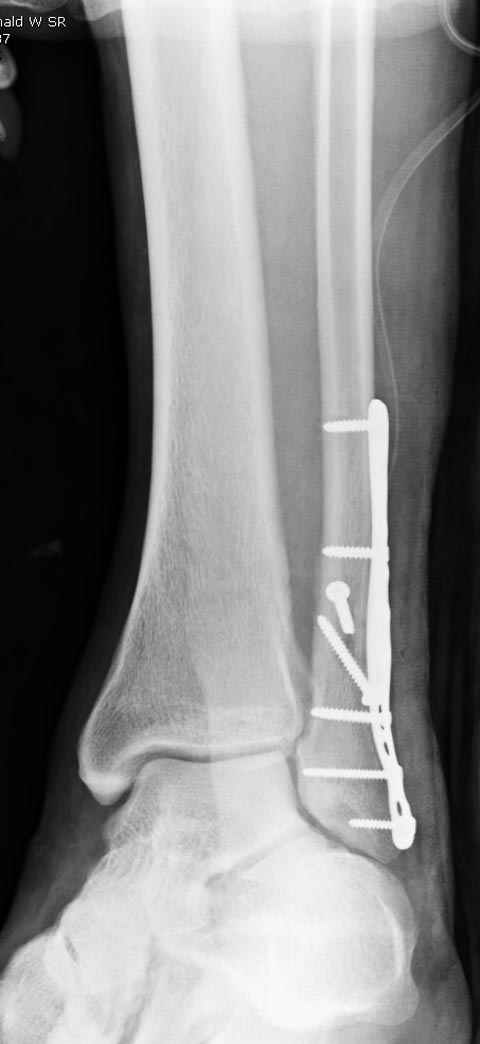

Уважаемые коллеги! Как и обещал, представляю плоды своей работы. Хвалиться особо нечем. Пошли задним

доступом сначала к м/берцовой кости, благодаря смещению линию перелома удалось сразу дифференцировать и по ней узким долотом (без молотка) мобилизовали отломки. Затем выделили задний край, там было проще пройти по линии перелома. Далее пластина по задней поверхности в дистальный отломок, винт проксимальнее пластины и дистрактором с трудом растянули отломки, ощущение было идеальной репозиции м/берцовой кости( доступен осмотр по задней и наружной поверхности), далее винты стандартно. Кстати, положение больной на боку: очень неудобно, но по-другому потом не повернуть на спину, чтобы сделать снимки в стандартных проекциях (ЭОПа нет). Затем дистрактор (два полукольца, спицы), репозиция заднего края, спонгиозный винт с шайбой, слишком проксимально, поэтому + еще один. Доступ к дельтовидной связке: рубец в передней порции, частично иссечен, шов. В общем, длительность операции 3,5 часа, а сказать, что все задуманное получилось, не могу.

А.Минервин.

Отличная, грамотная работа, поздравляю, я бы держал в гипсовой повязке до трех недель, затем разработку сустава без нагрузки, нагрузку при такой фиксации,

думаю, можно начать в 6 недель.

Все таки нужно было стянуть ДМС. Судя по снимкам остался подвывих.

Отправитель: Alexander Chelnokov 16 Март 2006, 17:18

Да все прилично получилось, и случай ведь запоздалый, так что все труднее было, чем обычно. Так что присоединяюсь к поздравлениям!